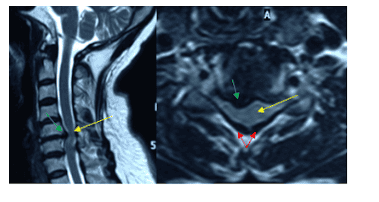

Cộng hưởng từ (MRI): Giúp đánh giá mức độ hẹp ống sống, chèn ép tủy sống; phát hiện tổn thương trong tủy như bướu ... Sự tăng cường độ tín hiệu của tủy gợi ý nhuyễn tủy hoặc tổn thương tủy vĩnh viễn.

Hình ảnh cộng hưởng từ (MRI) đánh giá mức độ hẹp ống sống